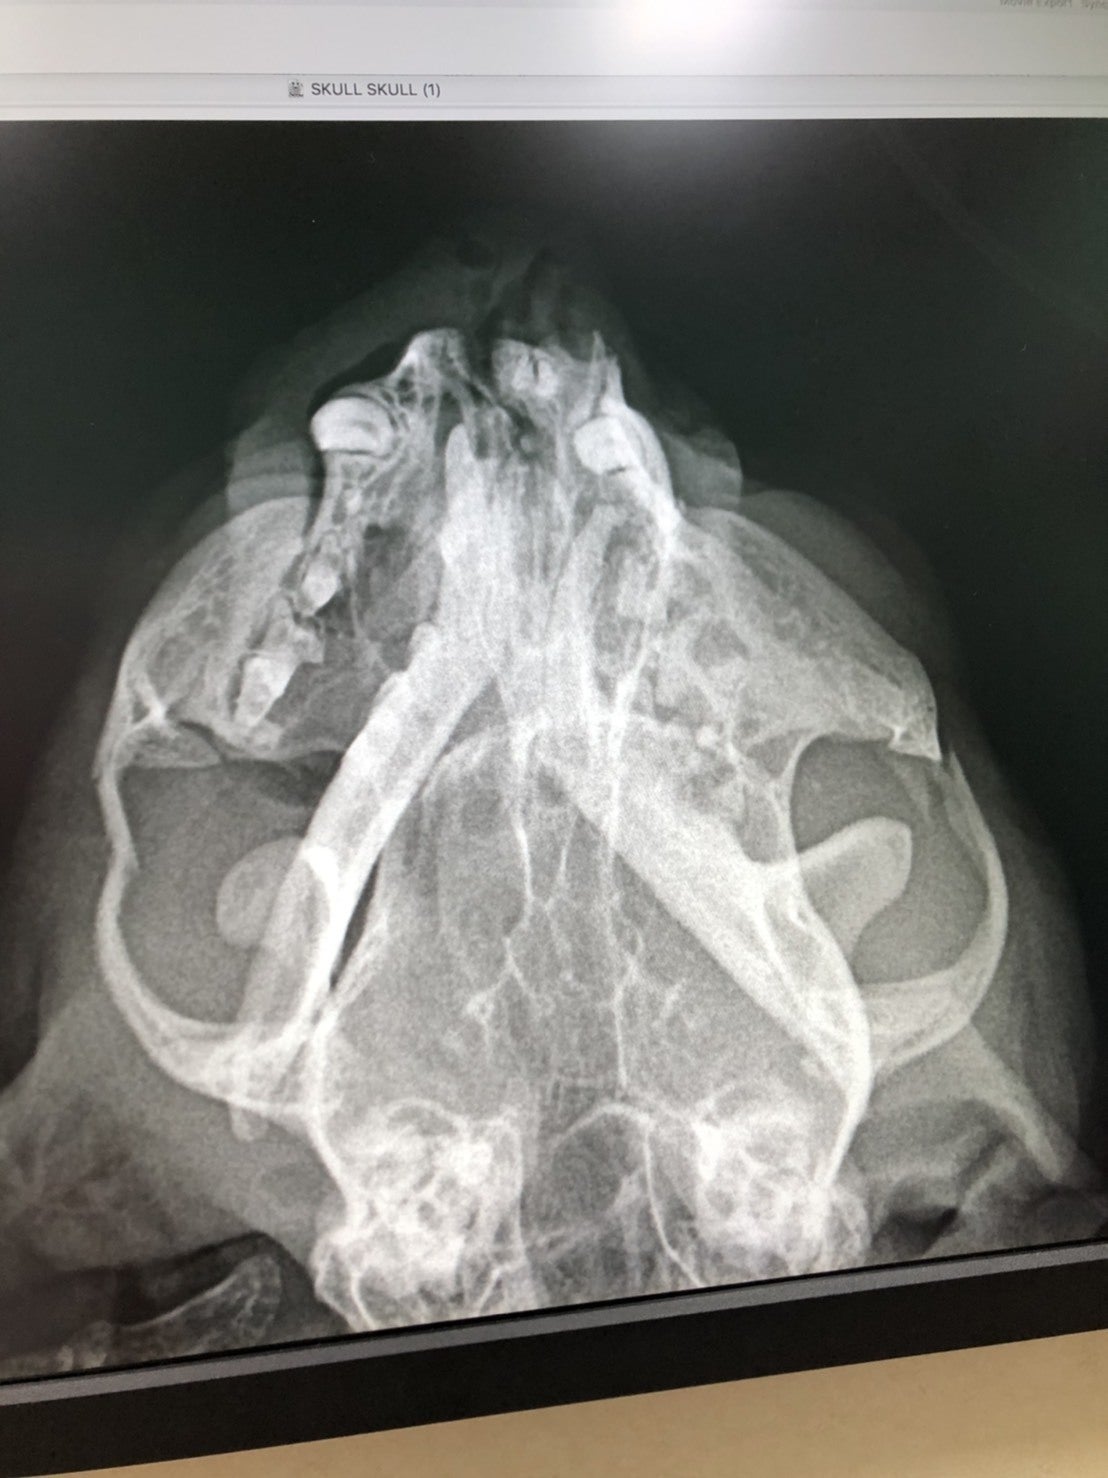

見つけた時の姿はとても酷く、傷口が化膿して顔は膿だらけで鼻からも夥しいほどの膿が流れ出ていました。